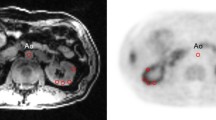

The MRI images were used to delineate volumes-of-interest (VOIs): (1) aorta descendens (below the arteria renalis), drawn by hand in several layers (2) left kidney, (3) right kidney, (4) left kidney cortex (5) right kidney cortex, (6) left kidney medulla and (7) right kidney medulla. VOIs (2–3) were carefully drawn by hand in each layer; all other VOIs were delineated randomly in about 30% of all layers by a threshold VOI selection tool. After image fusion, the FDG concentrations in the according VOIs were measured in units of standardized uptake values (SUV); the time activity curves (TACs), reflecting the tracer concentration over time, were exported for further analysis. In Fig. 1, a fused PET/MRI image of a typical transplant kidney with the corresponding TACs of transplant and healthy control kidneys are presented. FDG TAC analysis was performed using an in-house Java-based tool (programmed with openjdk version 1.8.0_162), for which the aorta input function (AIF) along with the TACs were used as inputs. TACs were smoothed with a Bezier filter and the AIF was fitted with a tri-exponential function starting from its peak.

Fused positron emission tomography and magnet resonance image (PET/MRI). (a) A delineated volume of interest (VOI) of the total kidneys is schematically indicated in blue. (b) FDG time activity curves in units of standardized uptake value (SUV). The curves show the average over all 13 measured transplant kidneys (bold blue line) ± one standard deviation (thin blue lines), and for comparison the average over 48 healthy kidneys (bold purple line) ± one standard deviation (thin purple lines). The general kidney performance (GKP) represents the FDG uptake between minute 2 and 3.

As depicted in Fig. 1a a VOI was drawn around the kidney after fusion of PET and MRI for calculating the distribution of FDG over time. The mean GKP of the kidney allografts and the healthy kidneys are shown in Fig. 1b. Comparing the GKP in transplanted and healthy kidneys, higher GKP was observed in healthy controls (4.5 ± 1.2 versus 5.6 ± 0.8, respectively), which was significant for the entire kidney (p = 0.0002) and the medulla (p = 0.0004), but no difference was found between the GKP of the cortex (p = 0.59). A difference between the total GKP in patients with low tubular damage (0 to 2) and patients with high tubular damage (3–5) of 22% was found, but this did not reach significance (4.1 versus 3.3, p = 0.17). Also in medulla GKP a non-significant difference of 29% (4.8 versus 3.6, p = 0.07) was seen.